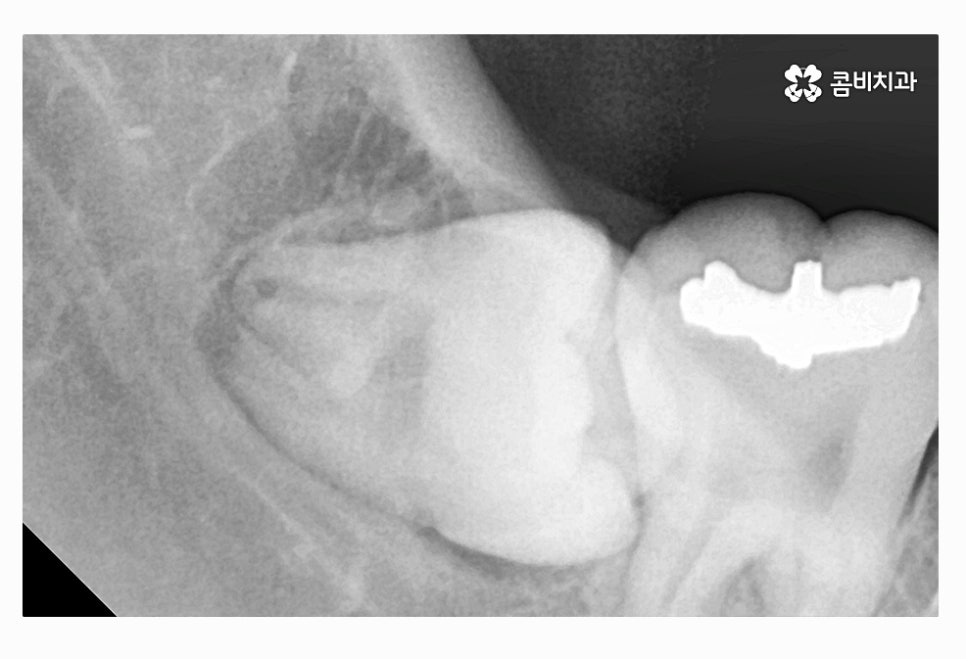

위 사진에서 보시는 것처럼 사랑니가 누워서 자라는 사례는

턱뼈가 좁은 한국인들에게 자주 나타나는 사례이며

음식물이 치아 사이에 끼거나 치석이 쌓이기 쉽기 때문에

청결 관리 미흡으로 인한 구강질환이 발생할 수 있어요.

사랑니가 누워서 자라는 경우에는 청결 관리를 떠나서

어금니 쪽으로 사랑니가 자라면서 주변에 염증을 발생시킬 우려도

있고 턱뼈 손상으로 이어지는 경우도 있기 때문에

사랑니 충치와는 무관하게 발치가 필요할 수 있는데요.

사랑니가 매복이 된 상태에서 위 사진처럼 부분적으로 돌출이 되어

사랑니 충치 심해지는 경우도 많고 주변 잇몸이 붓고

염증이 심해져서 잇몸에도 안 좋은 경우가 많이 있어요.